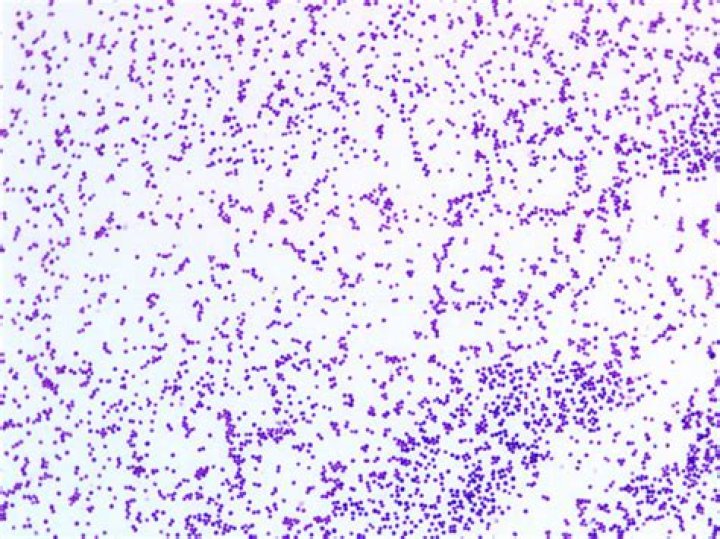

S. aureus is a facultatively anaerobic, Gram-positive coccus, which appears as grape-like clusters when viewed through a microscope, and has round, usually golden-yellow colonies, often with hemolysis, when grown on blood agar plates.

Staphylococci are irregular (grape-like) clusters of cocci (e.g. Staphylococcus aureus). Tetrads are clusters of four cocci arranged within the same plane (e.g. Micrococcus sp.).

Staphylococci The cocci are arranged in grape-like clusters formed by irregular cell divisions in three plains.

Staphylococcus is a genus of Gram-positive bacteria in the family Staphylococcaceae in the order Bacillales. Under the microscope, they appear spherical (cocci), and form in grape-like clusters. Staphylococcus species are facultative anaerobic organisms (capable of growth both aerobically and anaerobically).